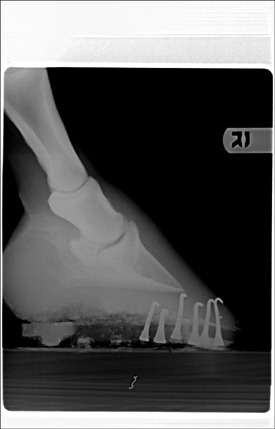

Posted on Wednesday, Mar 23, 2005 - 10:41 am: Here's another one in case this works.

Posted on Friday, Mar 25, 2005 - 10:20 am: I can see he has remarkable calcification of the lateral cartilages (probably not significant) and the 10:41 image appears to have something going on around the coffin joint, but I cannot make out any detail.These images were originally 8 by 10 and for the detail we need, for the type judement you want, it is going to require a full size original on a screen, only then can I compare these lesions with those I have seen in the past. Let's try to get this on firmer ground. What lesions did your veterinarian diagnose from the above radiographs that made him make the above statement? DrO |

Posted on Tuesday, Mar 29, 2005 - 11:22 am: You appear to be making sense but I don't understand the vets thought about degenerative joint disease of the coffin bone bone healing: this is chronic arthritis. Are you sure you are on the same wavelength with your vet?Looking at your radiographs only raises more questions. Looking at rf2, which is an oblique of the foot, at first glance looks like changes consistant with coffin jt arthritis but...we have to remember that the lateral cartilages are ossified. For those follwing this discussion it is the 10:41 am radiograph above. I cannot be sure we are not seeing the overlying lateral cartilage, making it appear that the joint has developed remarkable osterphytes. In fact I find this a likely explanation but would require further radiography to prove or disprove. I don't see evidence of DJD of the coffin joint evident on the lateral (straight from the side) or ap (the one taken directly from in front of the foot) and the other obliques are too underexposed to read this aspect of the study. Though we do not see it in the other views, often the first place to see these changes are in the oblique shots. I recommend the vet take a series of obliques that slowly work around the foot to differentiate these 2 possiblilities. Yes you can palpate the side bone. Look on the ap radiograph and it will show you exactly where to feel them. DrO |

Posted on Thursday, Apr 7, 2005 - 10:02 am: Assuming we are talking about the same thing, I disagree with your veterinarian. If you look closely at the side bone in the first (lateral) radiograph there is a little notch at the top. In the second (oblique) shot the area that looks like severe DJD changes of the coffin joint also has a notch at the top: they look like the same notch to me.I don't think the relationship of the coffin bone to most of the sole is bad, but agree with the farrier, the toe needed chopping off in front. Just off the front, I would not thinning the sole uner at the toe. DrO |